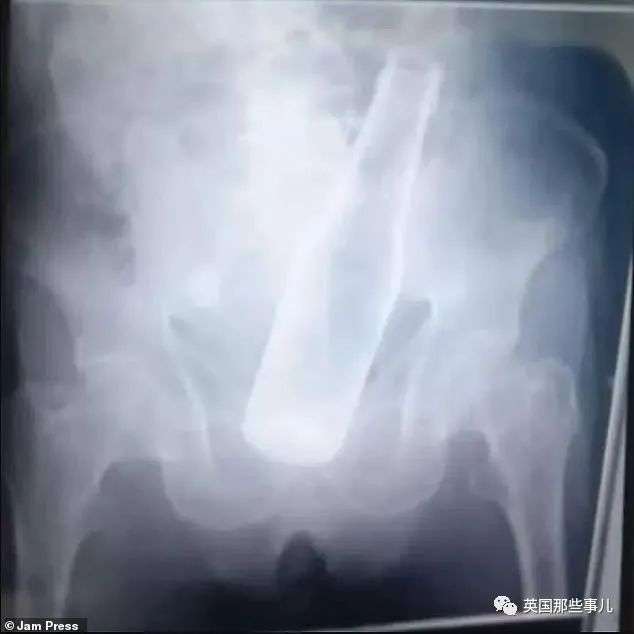

近日,委内瑞拉一名79岁大爷,被送往当地的La Ovallera医院急诊室。

这位未透露姓名的大爷,看起来非常痛苦的样子。

医生检查后发现,原来是有个啤酒瓶卡在大爷的体内。

对此,大爷解释称,啤酒瓶是小偷塞进去的。

随后,大爷被转移到距离第一家医院约六英里的Maracay医院接受治疗。

据悉,大爷接受了“紧急手术”,但没有提供更多细节。

在某些情况下,如果卡在直肠中的异物离肛门足够近,可以用手将其取出。

但主要问题之一是,物体和直肠壁之间存在很强的吸力,这就给移除工作带来了困难。